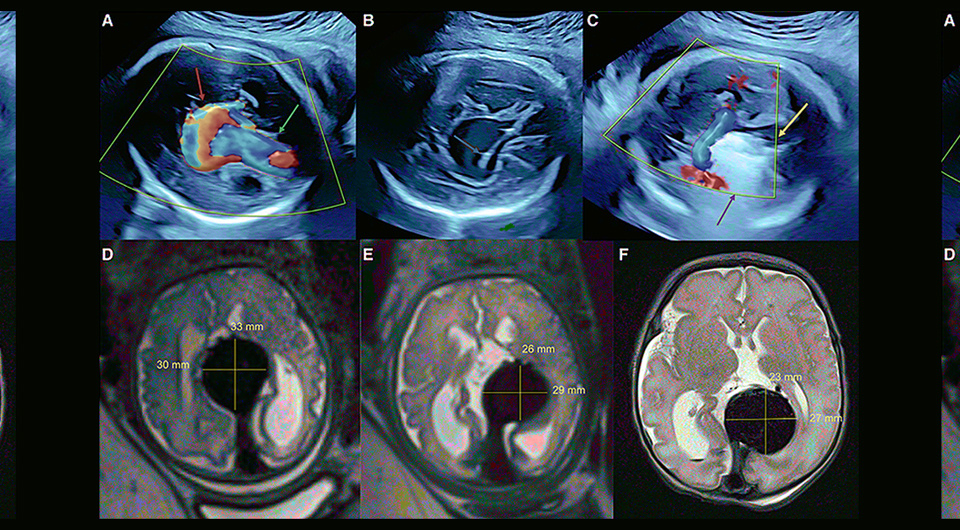

Американские хирурги провели первую в мире внутриутробную операцию по эмболизации артериовенозной мальформации большой мозговой вены — вены Галена. По сообщению, опубликованному в журнале Stroke, ребенок родился недоношенным, однако операция предотвратила тяжелые поражения головного мозга, связанные с пороком, которые могли произойти во время родов или после рождения.

Врожденный порок развития (артериовенозная мальформация) вены Галена (большой мозговой вены) встречается довольно редко — примерно у одного из 25 тысяч новорожденных. При этом такая аномалия имеет крайне неблагоприятный прогноз и ведет к летальному исходу вскоре после рождения. Дело в том, что между близлежащими артериями и веной Галена образуется шунт, по которому в венозное русло поступает много артериальной крови. Во внутриутробном развитии такое патологическое соединение сосудов практически не влияет на жизнедеятельность плода — из-за низкого сопротивления плаценты поток крови из аорты в головной мозг не такой интенсивный.

Однако сразу после рождения и первого вдоха кровоток через мозговые сосуды резко возрастает, увеличивается венозный возврат к сердцу. Патологический шунт приводит к тому, что нарушается внутричерепной отток крови, а к сердцу возвращается больший объем крови. Из-за этого у новорожденных с мальформацией вены Галена к сердцу возвращается много венозной крови, что может осложниться легочной гипертензией, а в левом желудочке снижается фракция выброса — органы начинают недополучать